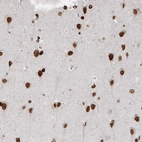

Immunohistochemistry analysis in human testis and skeletal muscle tissues using HPA060744 antibody. Corresponding CHD2 RNA-seq data are presented for the same tissues.